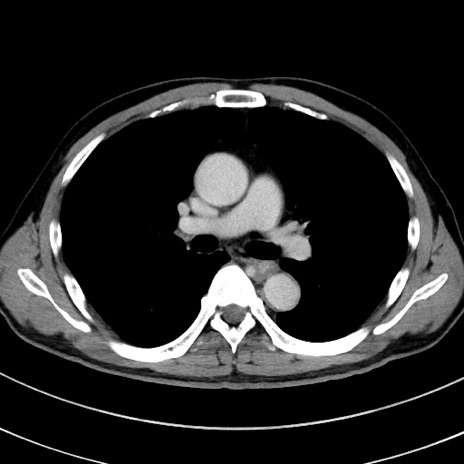

症例8(横断像)

【症例】 60歳代男性

【主訴】 黒色吐物

【現病歴】 4日前から嘔気自覚、2日前の朝食後にも嘔気あり、自分で手で嘔吐反射起こし嘔吐したところ血が混ざっていたため受診。

【既往歴】 5年前汎発性腹膜炎を伴う急性虫垂炎で手術、高血圧、前立腺肥大症、高脂血症

【身体所見】 腹部正中に手術癩痕あり 腹部平坦・軟圧痛なし膨満感あり

【データ】WBC 8400、CRP 4.54